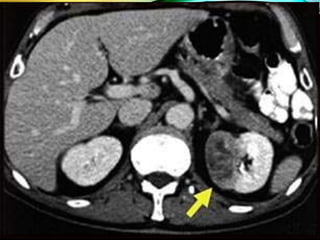

TOMOGRAFÍA COMPUTADA

• Principal indicación:

• Estudio de masas renales o suprarrenales no claramente

definidas por la ecografía.

• Valoración de traumatismos renales.

• Valoración de procesos parenquemitasos

TOMOGRAFÍA COMPUTADA • Principalindicación: • Estudio de masas renales o suprarrenales no claramente definidas por la ecografía. • Valoración de traumatismos renales. • Valoración de procesos parenquemitasos